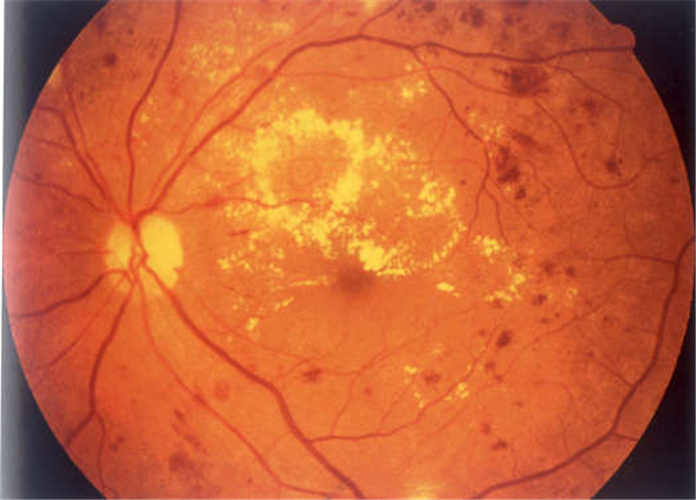

糖尿病人視網膜脫落